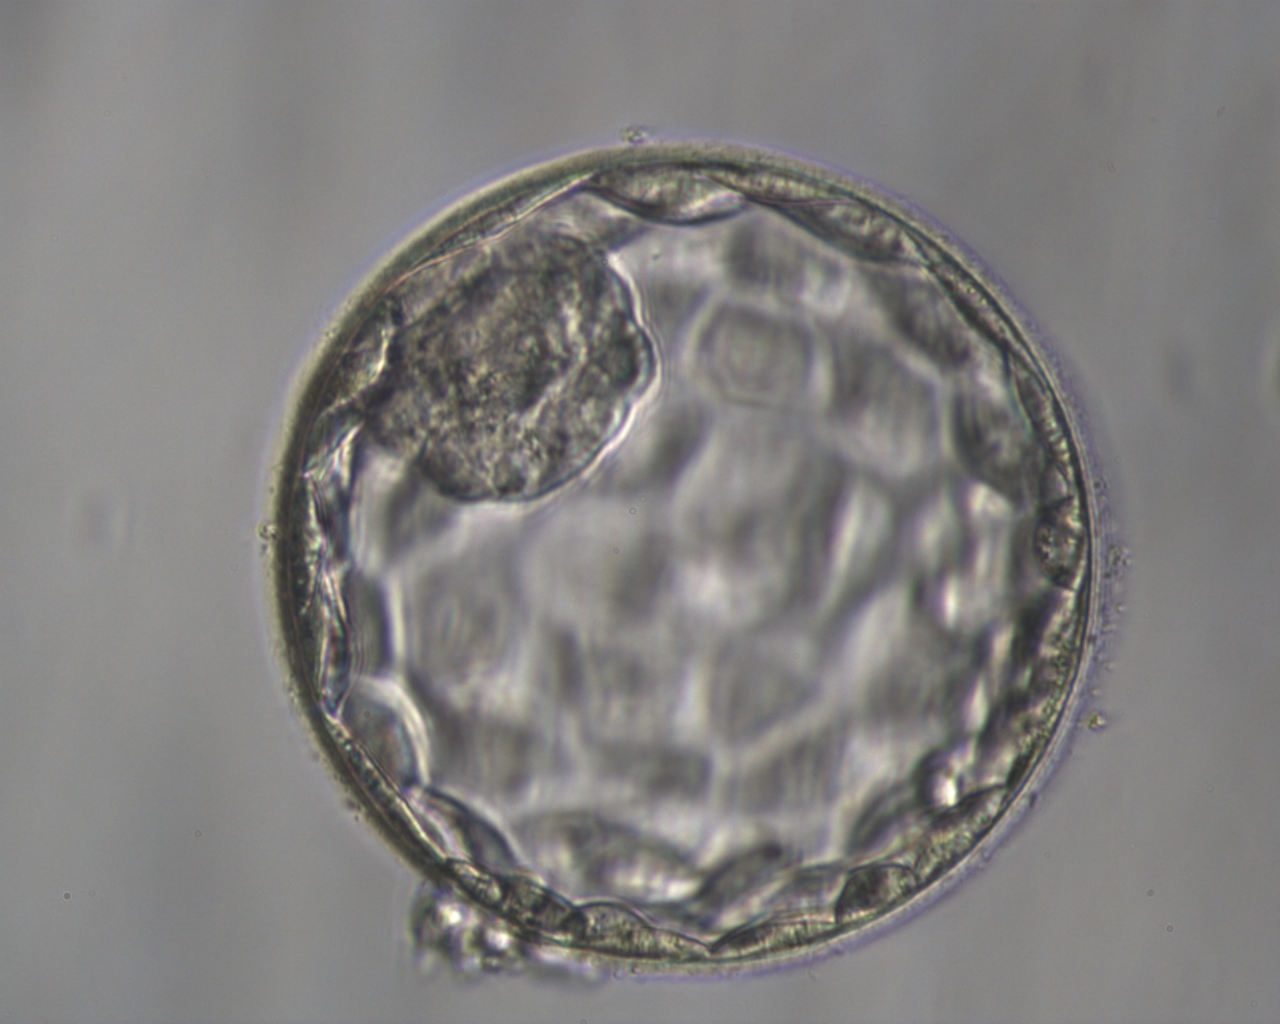

Brutschrank weiterkultiviert. Im Laufe des Tages beginnt dann die Zellteilung. Überzählige entwicklungsfähige Vorkernstadien können nach Rücksprache mit Ihnen eingefroren werden (siehe Kryokonservierung). Wird die Kryokonservierung von Ihnen nicht gewünscht, werden diese verworfen. Die Embryonen werden bis zu Tag 5 kultiviert und täglich beobachtet. So ist eine gute Differenzierung und die Auswahl eines optimal entwicklungsfähigen Embryos möglich. Dies kann auch im Embryoskop erfolgen, wo mit Hilfe kleiner Kameras jeder Embryo im Brutschrank rund um die Uhr ohne Störung beobachtet werden kann.

4. Embryotransfer

Beim Embryotransfer wird in der Regel ein Embryo mit einem weichen Plastikschlauch unter Ultraschallsicht in die Gebärmutterhöhle eingesetzt. Wir empfehlen den Transfer von einem guten Embryo. Überzählige gute befruchtete Eizellen oder Embryonen können kryokonserviert werden. Beim Transfer von 2 Embryonen entwickelt sich bei 20% der Schwangeren eine risikoreiche Zwillingsschwangerschaft. Die statistische Schwangerschaftswahrscheinlichkeit liegt zwischen 30-40 %. Allerdings sinkt diese Schwangerschaftsrate ab dem 40. Lebensjahr der Frau.